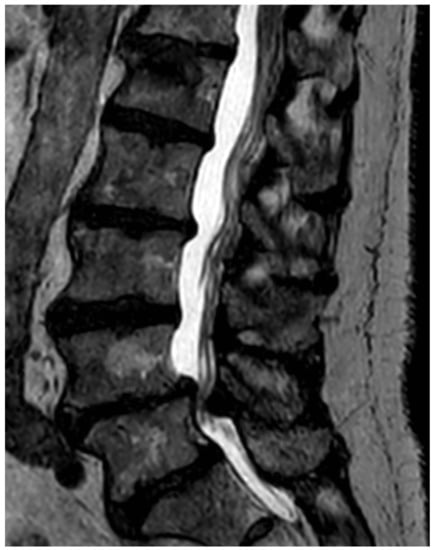

After the patient list was completed, the MRI images were assessed by a radiologist with several years of experience in reading MRIs of the spine. Figure 1 shows a typical sagittal, T2-weighed image of the lumbar spine with advanced signs of degeneration.

We deliberately decided against diagnosing arthritis of the facet joints in this project because consistent diagnostic criteria have yet to be developed. Figure 1 shows a typical sagittal T2-weighed MRI image of the lumbar spine.

Figure 1. Typical sagittal T2 sequence of a lumbar MRI with signal-attenuated and reduced-height intervertebral discs, evidence of multisegmental disc bulging and degenerative spinal stenosis in segment L4/L5. Additionally, typical vertebral haemangioma at L4.